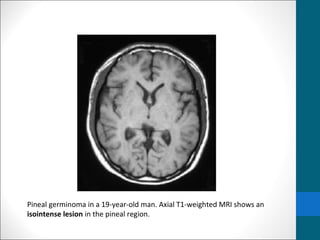

Pineal germinoma in a 19-year-old man. Axial T1-weighted MRI shows an

isointense lesion in the pineal region.

Germinoma …..MRI findings •T1/T2: • Usually isointense relative to cerebral gray matter •Occasionally • T1:hypointense • T2:hyperintense • I/V injection of gadolinium-based contrast material, • homogeneous and intense enhancement is seen. • contrast-enhanced MRI (subarachnoid seeding of germinomas.)